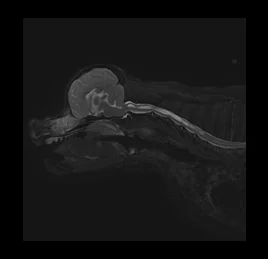

• MRA- 뇌혈관 조영술